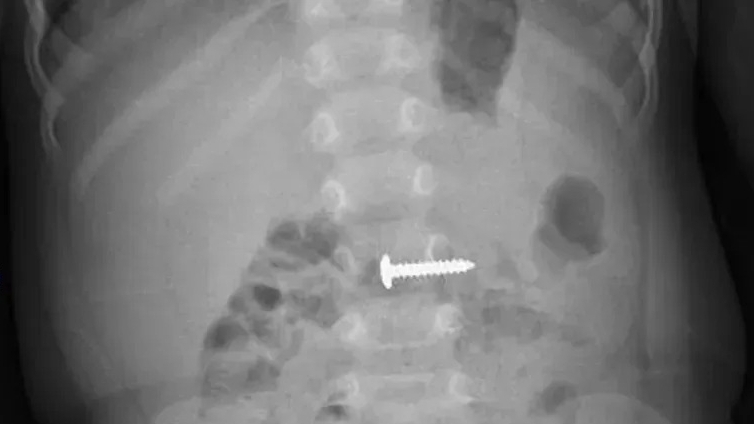

Trước cô gái 22 tuổi này, bệnh viện cũng xử trí một trường hợp nhiễm trùng khi phẫu thuật thu gọn quầng vú tại một cơ sở thẩm mỹ. Cô gái 23 tuổi bị phì đại vùng ngực, chi phí phẫu thuật hết khoảng 5 triệu đồng.

Sau phẫu thuật, người bệnh có tình trạng chảy dịch mủ, vết mổ bị toác, nứt, làm cho vết mổ bị hở và nhiễm trùng. Cơ sở thẩm mỹ cũng điều trị cho bệnh nhân, khâu vết mổ vài lần nhưng tình trạng nhiễm khuẩn nặng thêm.

Vào Bệnh viện đa khoa Đức Giang, bác sĩ phải phẫu thuật cắt lọc, làm sạch ổ mủ, cho bệnh nhân dùng kháng sinh, tiêm phòng, truyền dịch. Tới ngày thứ 5, vết thương tiến triển tốt, hết tình trạng chảy mủ, chảy dịch. Cô gái phải điều trị tại bệnh viện hơn hai tuần, mất thời gian hơn so với các ca nhiễm khuẩn thông thường.